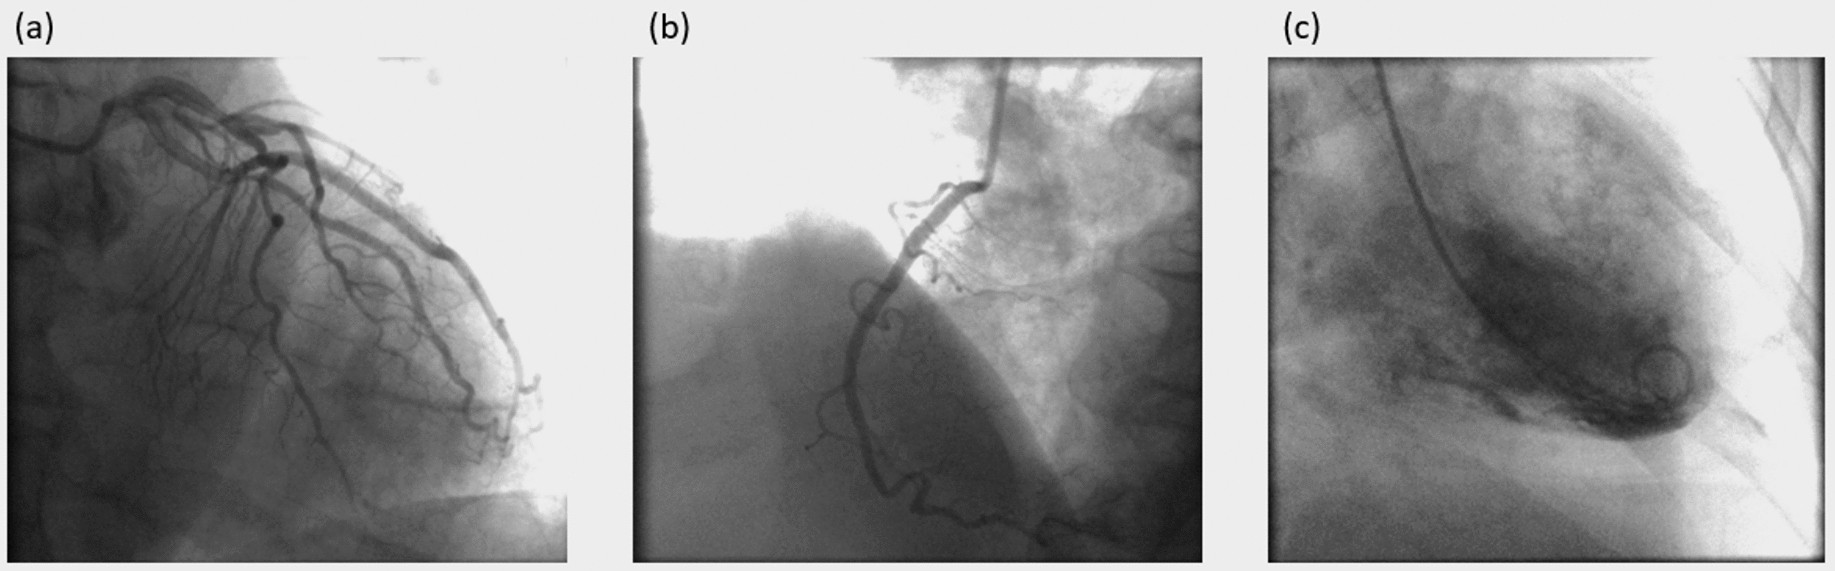

Angiographic frame after injection of contrast agent. (a) Angiogram of the left coronary artery (b) Angiogram of right coronary artery (c) Angiogram of the left ventricle.